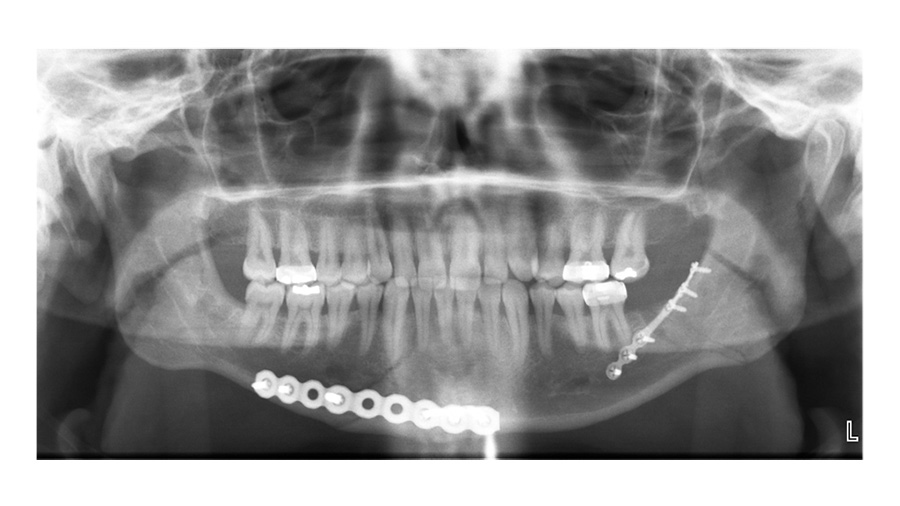

Dr. Hopper: Is this an early postoperative film where you decided to take the Erich arch bars off? Or is this after healing?

Dr. Susarla: This is an early post-operative film, and in this patient, we did take the Erich arch bars off at the end of the case. We were very confident in the stability of the fixation and the patient seemed fairly reliable. So that's a decision I think that every surgeon struggles with at the end of the case like this is, are you confident enough in your fixation to not have the patient in their maxillary fixation postoperatively?

So, you have your Panorex - what are you looking for on your PA film here?

Dr. Susarla: The PA film—what I'm looking for is just the splay at the inferior border. One of the advantages of the Panorex is that it's sort of the workhorse for dentoalveolar imaging, particularly for the mandible. It shows you the condyles, it shows you the inferior border, it shows you the teeth, and it can show you the positioning of the fixation relative to the roots of the teeth.

One of the downsides of the Panorex is that it doesn't show you the transverse dimensions. If there's a little bit of lingual splaying, you might not be able to see that as well. My protocol is, particularly in young patients, if there's no compelling reason to get a postoperative CT scan, then I just get plain film imaging to verify to myself that the reduction is adequate and that the hardware looks okay.

And I'd like to get two planes of imaging, so a Panorex, and in this case, a PA ceph[alogram] to be able to show the entirety of what you would imagine three dimensionally or the information you get from a 3D CT scan just with a lower radiation dose.